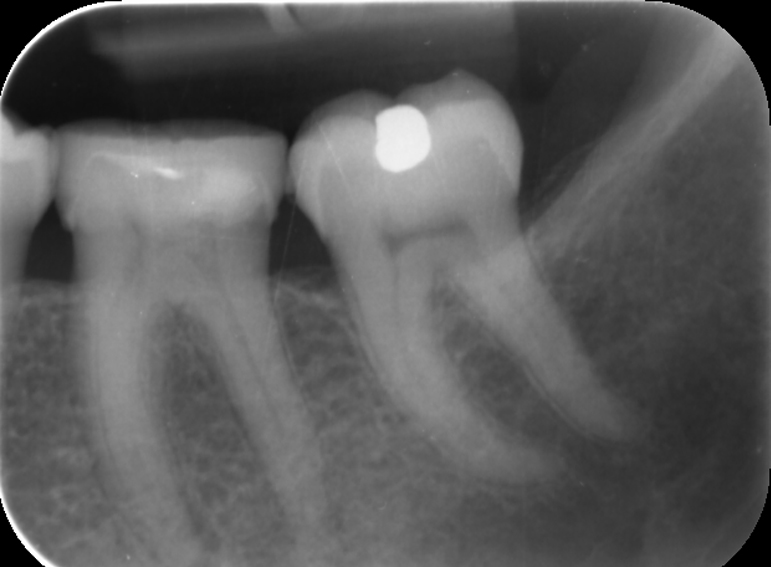

Amalgam restoration of an access cavity of a crowned molar